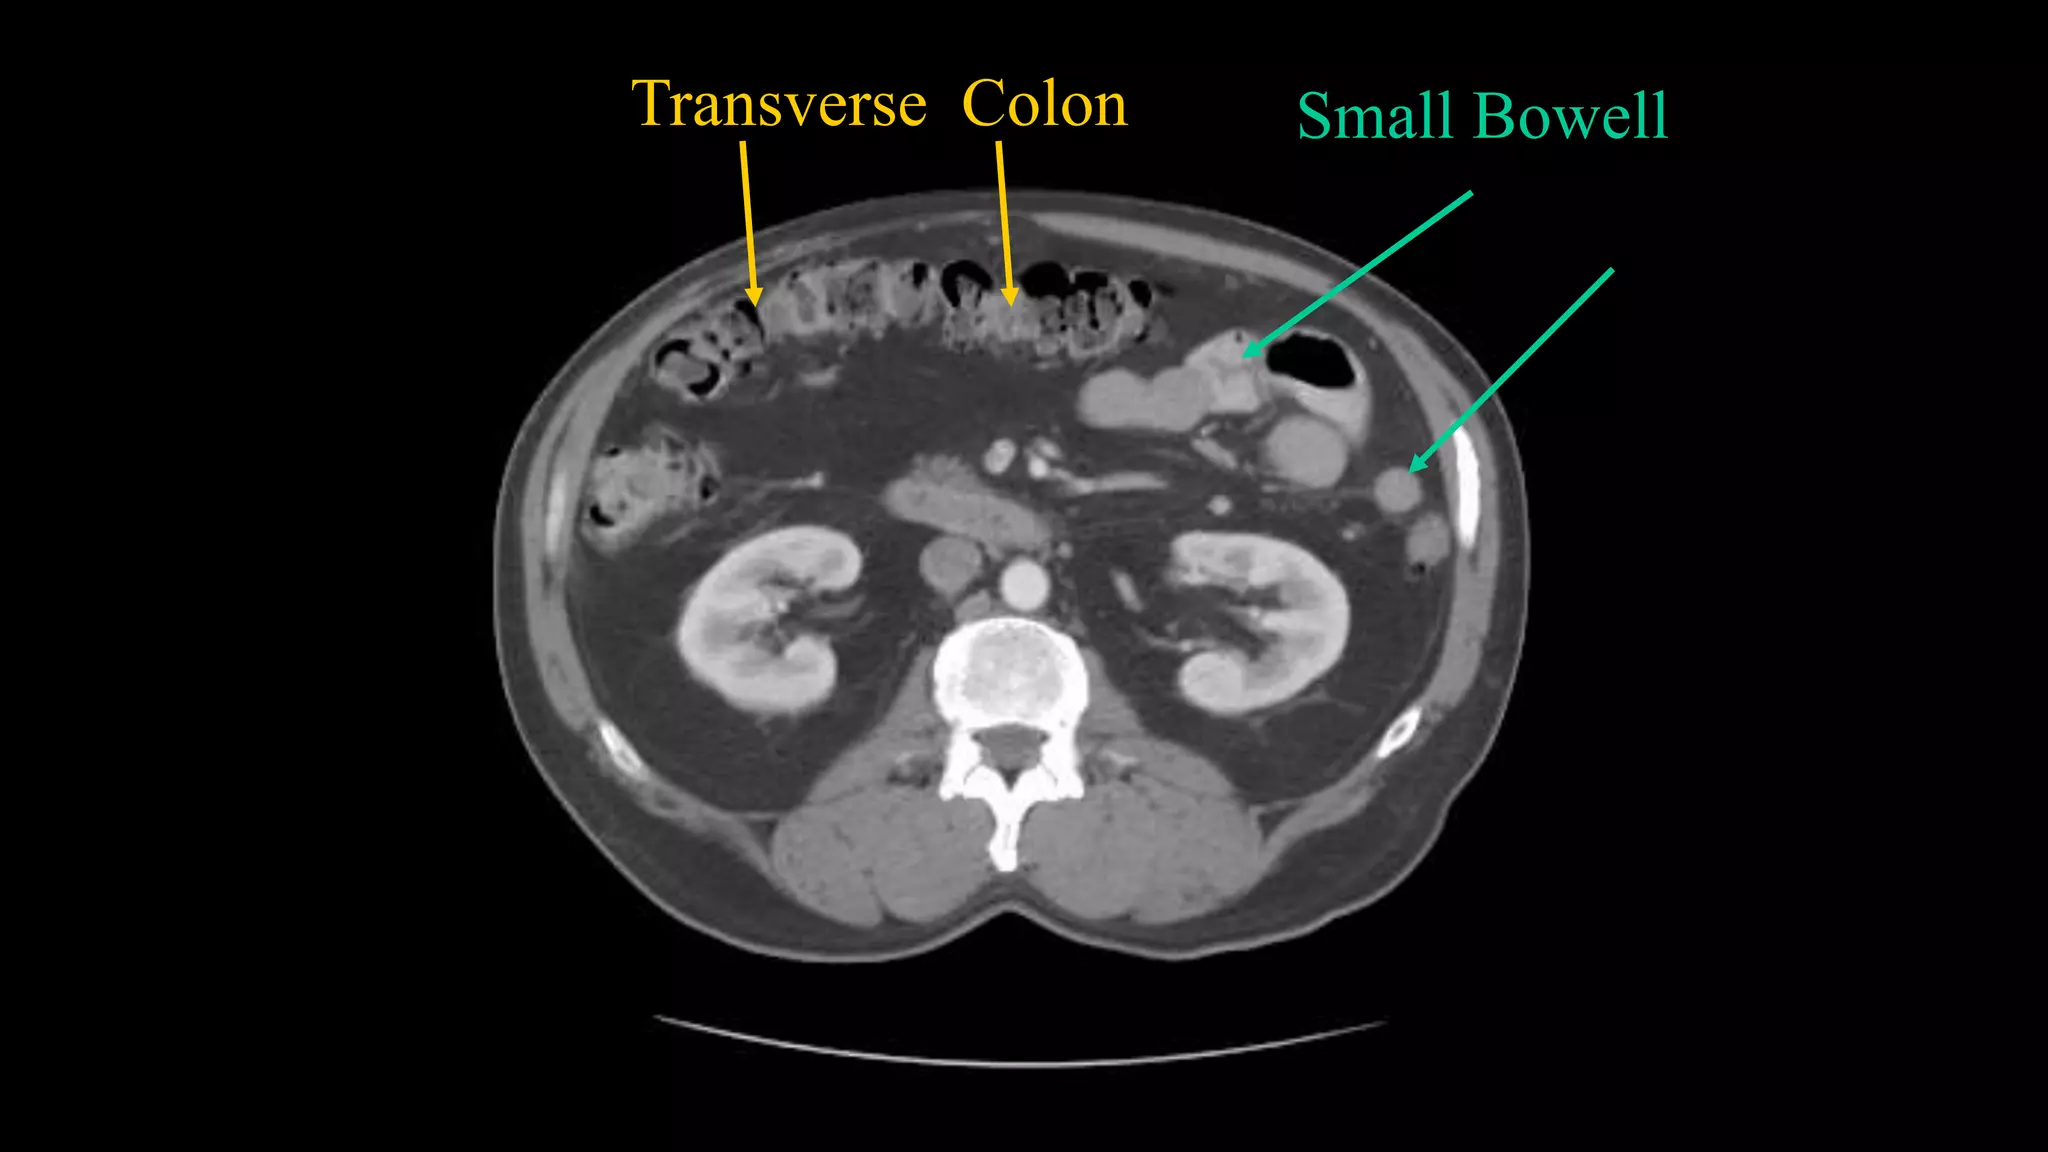

Transverse Colon Small Bowell

Superior Mesenteric Vein– follow it up as it joins the Splenic Vein to form the Portal Vein